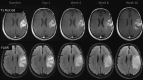

Fig 2.

Pseudoprogression. A 63-year-old man with GBM. A follow-up MR imaging examination performed 7 months after RT-TMZ demonstrates increased lesion size. The histopathology samples (not shown) demonstrated a mixed tissue with treatment-related changes, associated with a few areas of viable tumor cells.